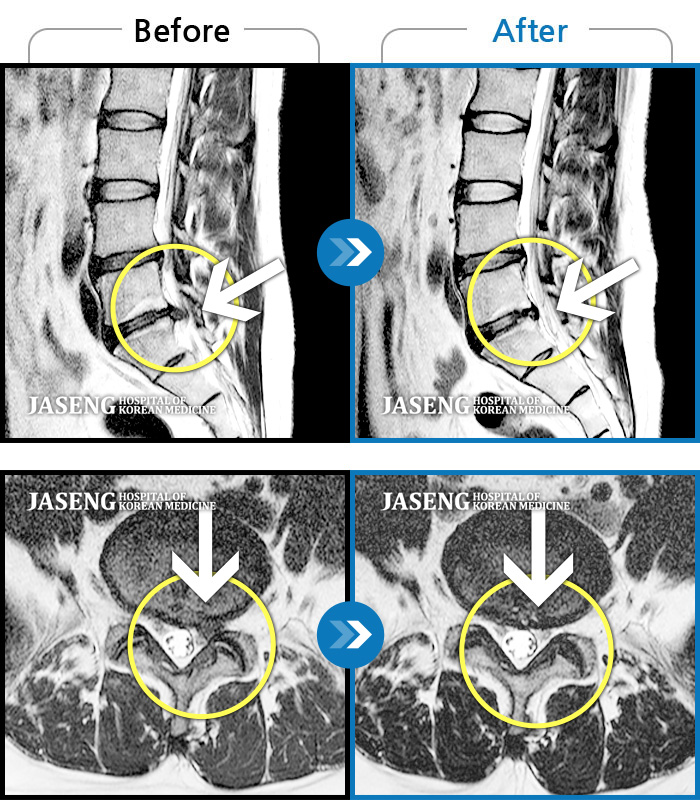

MRI 치료사례

앉지도 서지도 못하는 극심한 요통, 하지방사통으로 응급실 내원